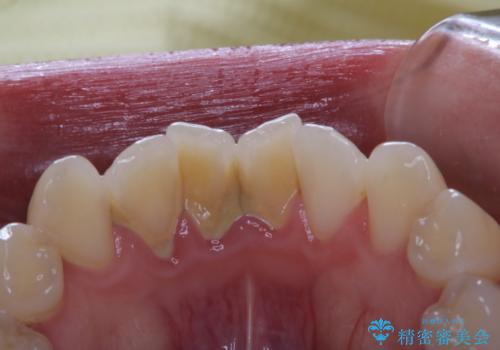

30代男性 PMTCで歯石取り